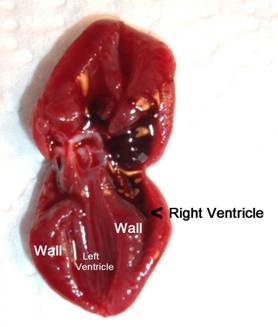

Step 9: Cut

the heart out of the chest and cut it in half longitudinally to measure the

width of the left ventricle and the thickness of its walls.

This is a normal heart showing the normal size This

heart has a mild case of hypertrophic This

picture shows a heart with a

relationship between the left ventricle and the cardiomyopathy,

where the walls of the left greatly

enlarged right ventricle, which is

thickness of its walls. ventricle

become thickened, narrowing the left caused

by high blood pressure in the

ventricle. This picture also shows the right

ventricle lungs, as well as

some thickening of the

which

pumps blood to the lungs. walls of the left ventricle. (The black stuff

is blood clots.)